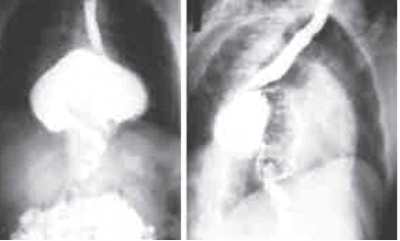

צילום חזה לאחר מתן חומר ניגוד יכול להראות מעי בחלל הצדר הדוחק את הריאה (תצלום 20.16). יש לזכור, שצילום בית החזה יכול להיות מפורש כתקין, או להדגים ממצאים שאינם ייחודיים לקרע בסרעפת (לדוגמה המוטורקס) בנפגעים רבים. ב-30% מהחולים צילום החזה תקין.